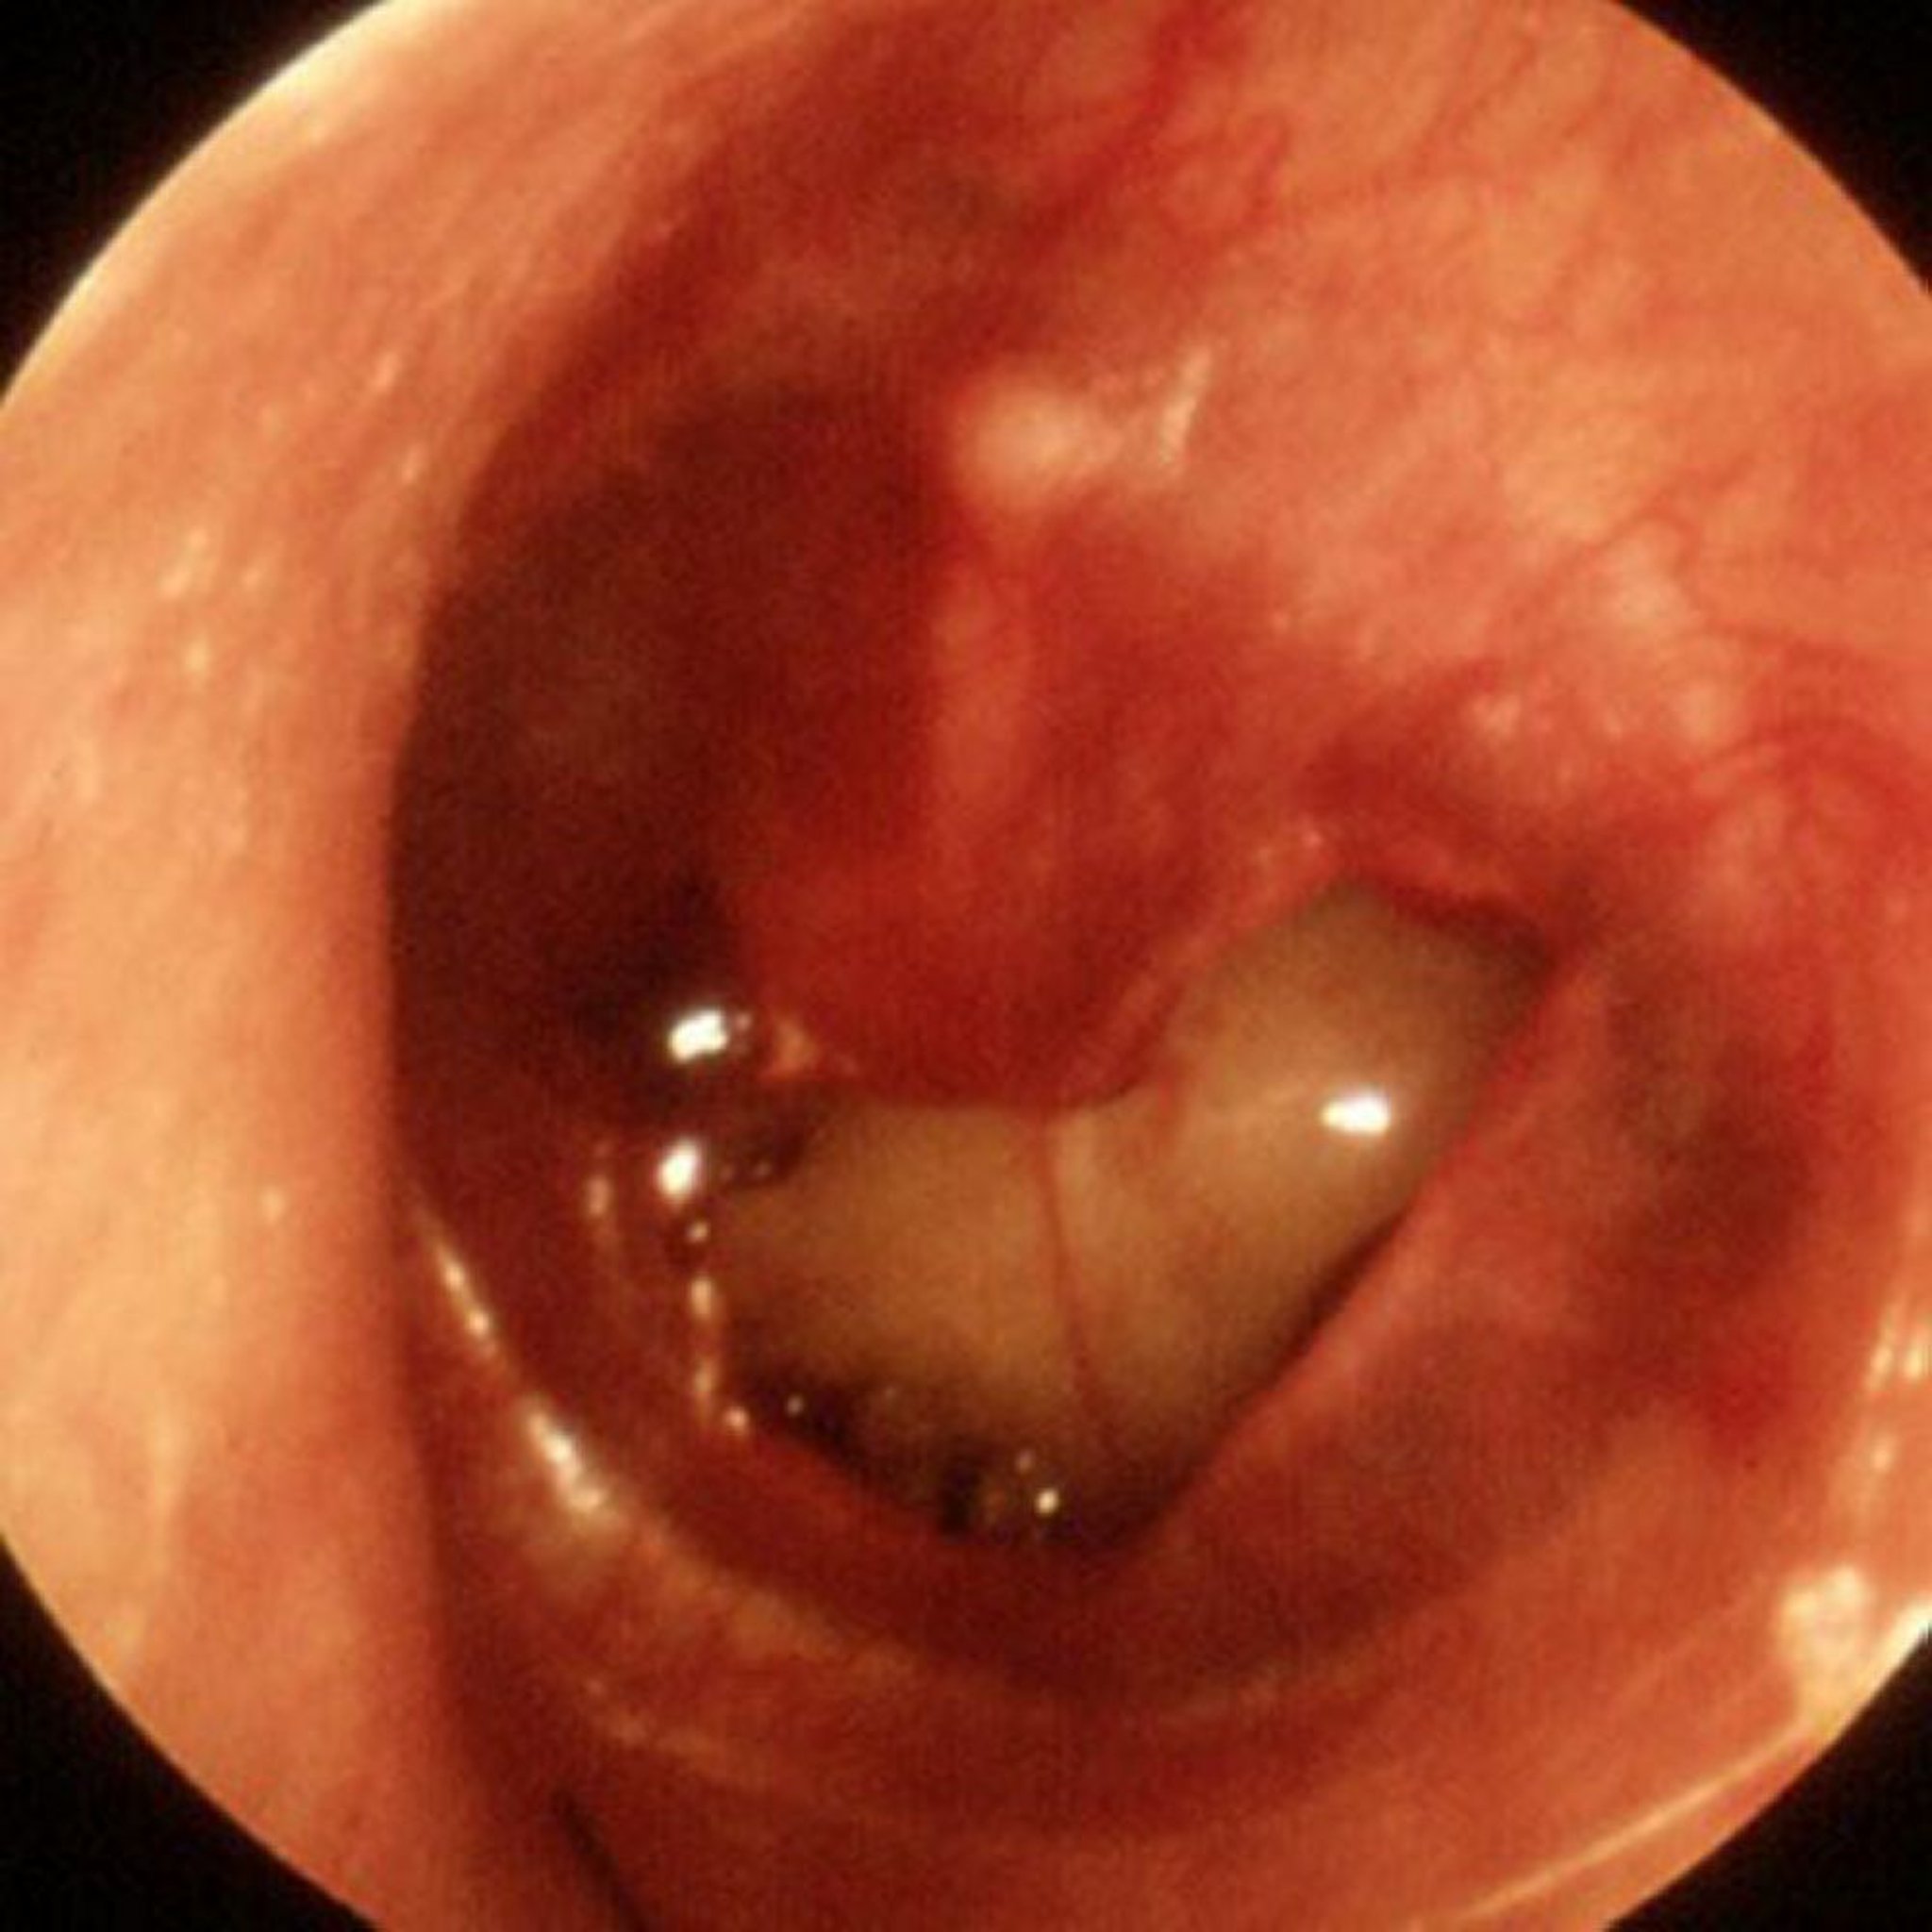

Perforation traumatique du tympan

Une grande perforation traumatique est visible sur cette image.

Image fournie par Piet van Hasselt, MD.